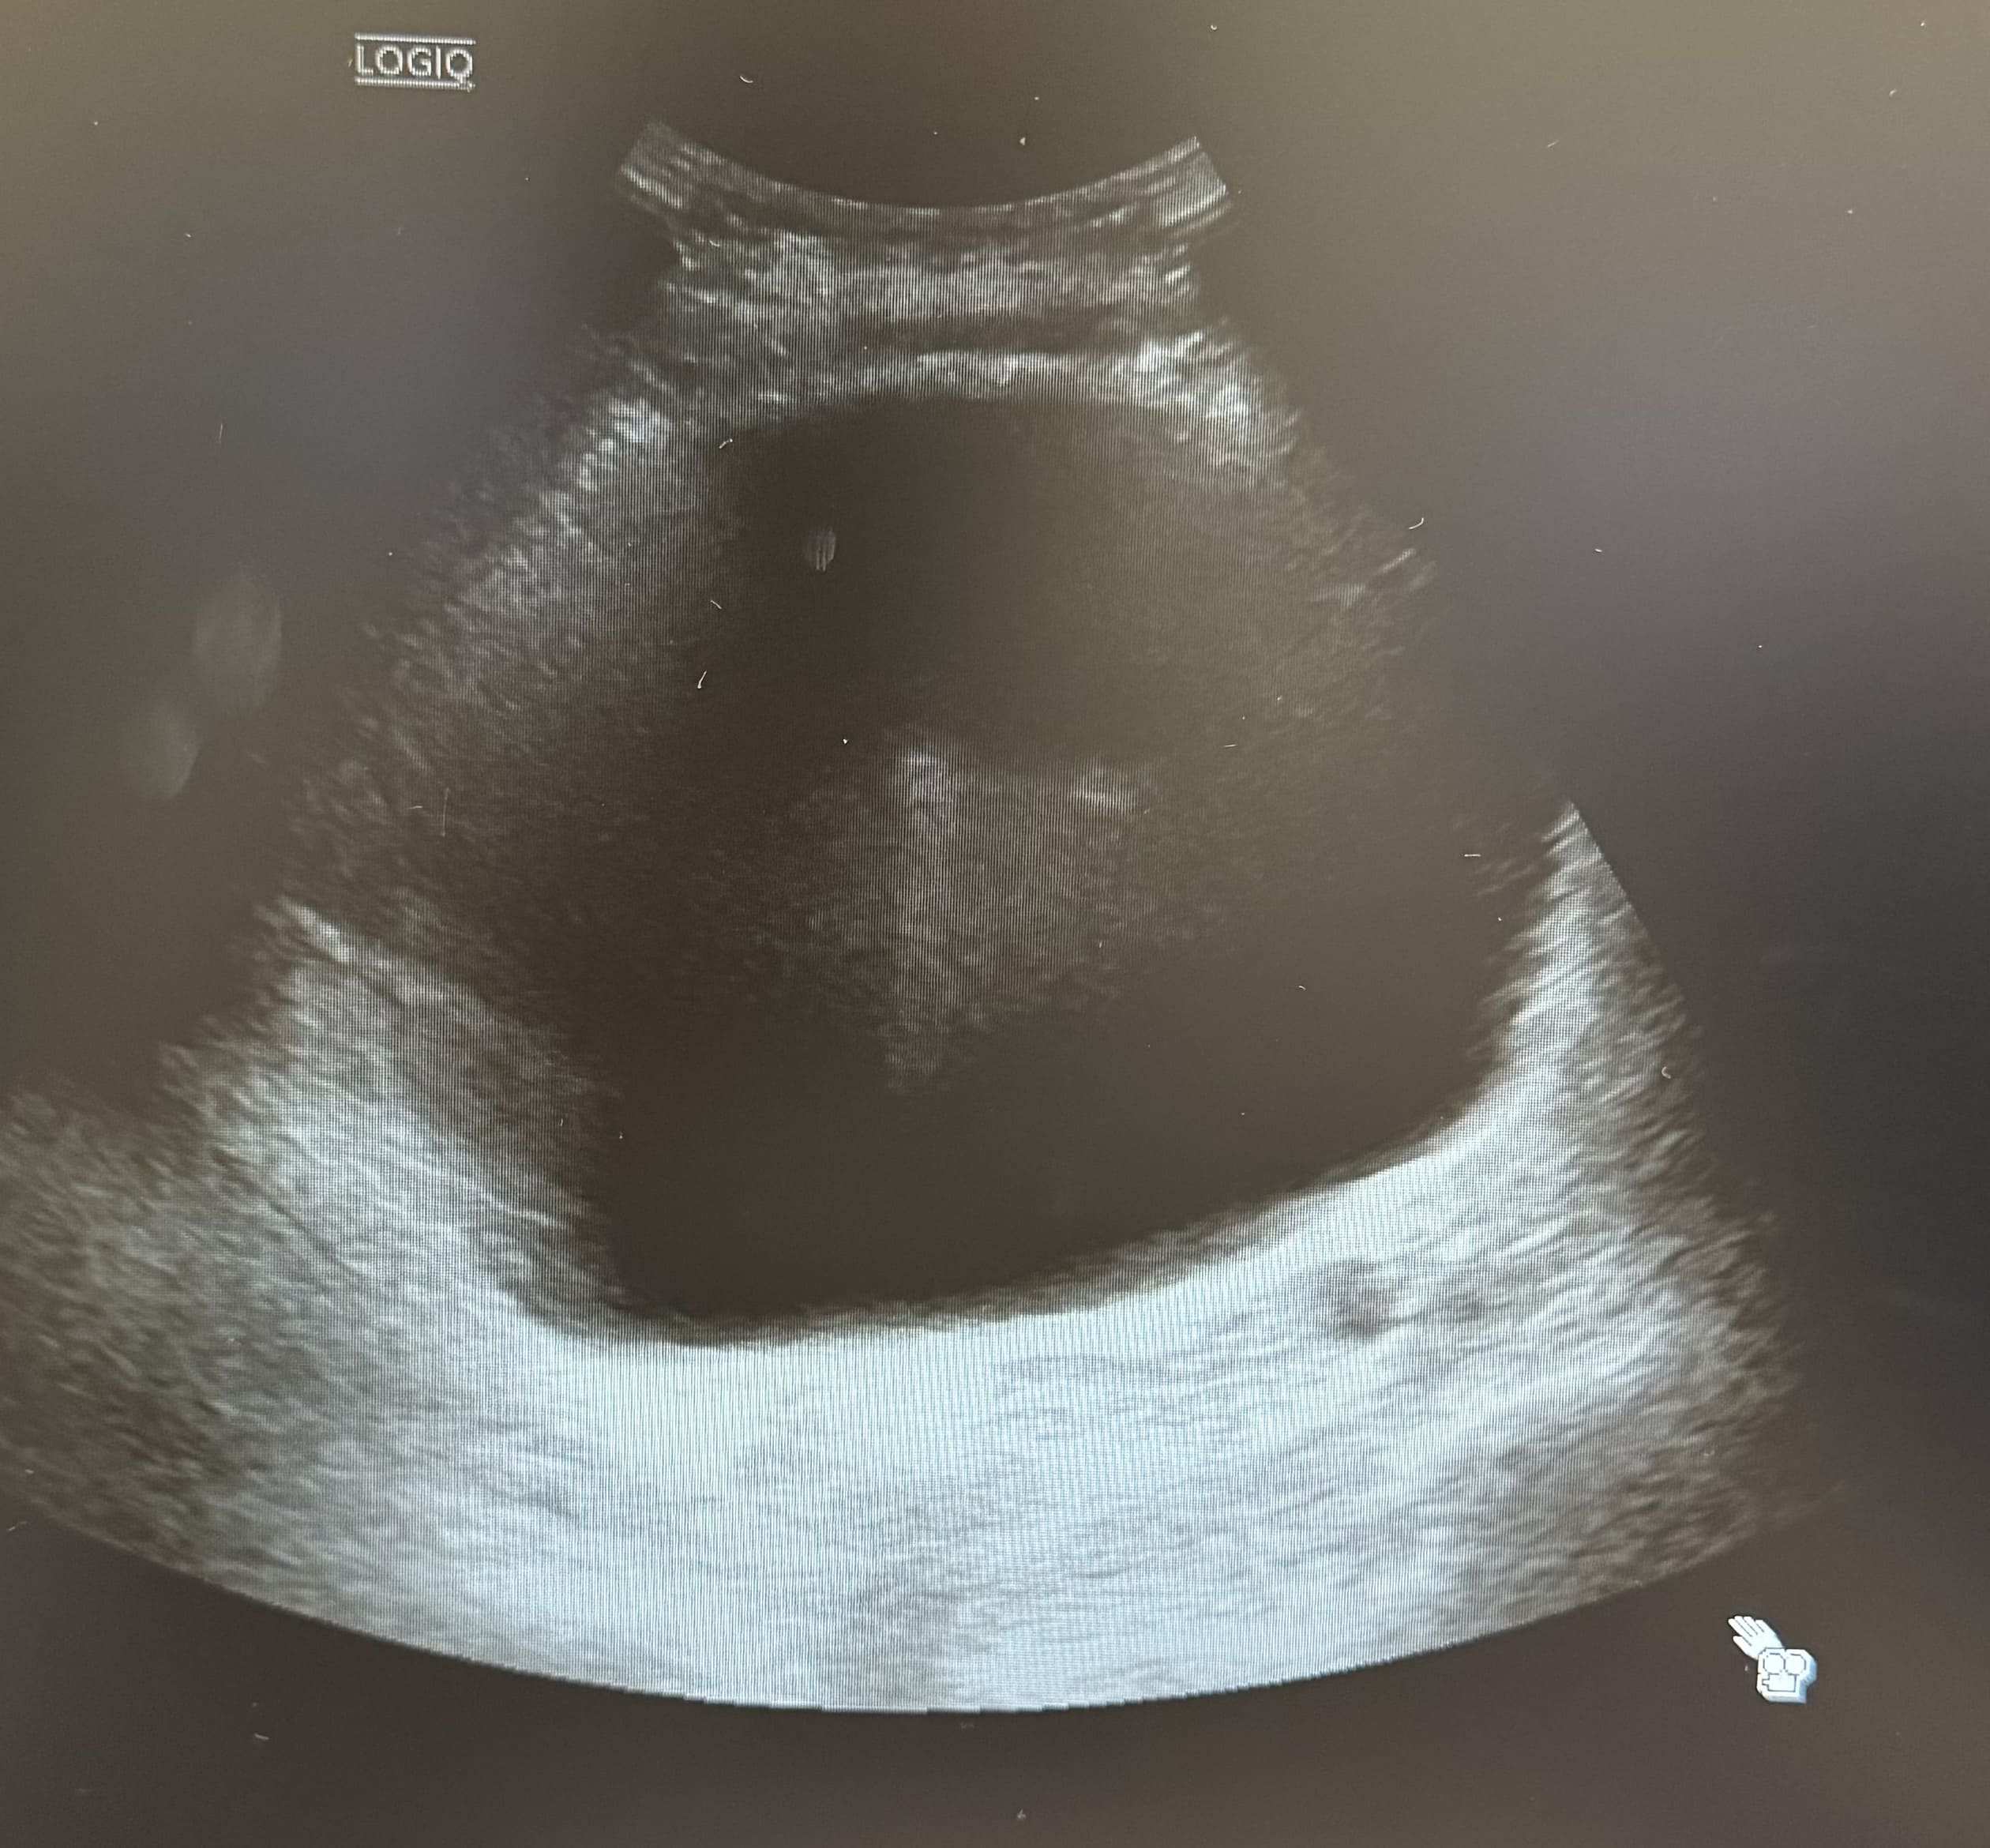

Hombre de de 73 años que acude a consulta de urgencias por dolor en fosa renal derecha desde hace 2 semanas irradiado hacia hemiabdomen derecho. En ese contexto pérdida de control de esfínter con escapes de orina especialmente nocturnos. Refiere además desde hace dos meses dificultad para el inicio de la micción, polaquiuria y nicturia asociadas sin disuria. Sin fiebre ni sensación distérmica en domicilio. No otra clínica por sistemas o aparatos.

Abdomen: masa en suprapúbica dolorosa a la palpación, no signos de irritación peritoneal, puñopercusión bilateral negativa.

Se sonda al paciente con salida de 500 ml. Se pauta fluidoterapia y control posterior del potasio 5,2 mmol/L.

La ecografía POCUS es una herramienta de gran valor en situaciones de emergencia y en el ámbito de la medicina de familia. Su uso permite un diagnóstico rápido de la retención urinaria, la evaluación del estado renal (hidronefrosis) y la identificación de la causa subyacente (hipertrofia prostática). Además, facilita intervenciones inmediatas y permite el seguimiento continuo en pacientes con enfermedades crónicas del tracto urinario.